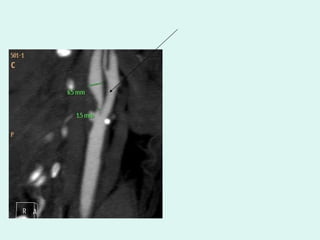

A figura 6A mostra o estreitamento acentuado da bifurcação da carótida com prometendo o fluxo sangüíneo. A 6B mostra ulceração de placa de ateroma que provoca liberação de fragmentos do trombo.

Dificuldades técnicas Dificuldades técnicas, como por exemplo, a semelhança dos coeficientes de atenuação do osso e do contraste não permite em muitos casos a precisa delimitação das lesões entre estas duas interfaces. Nestes pontos a análise baseia-se nos imagens fonte, bidimensionais

IMAGEM FONTE  BIDIMENCIONAL

Dificuldades técnicas Dificuldadestécnicas, como por exemplo, a semelhança dos coeficientes de atenuação do osso e do contraste não permite em muitos casos a precisa delimitação das lesões entre estas duas interfaces. Nestes pontos a análise baseia-se nos imagens fonte, bidimensionais